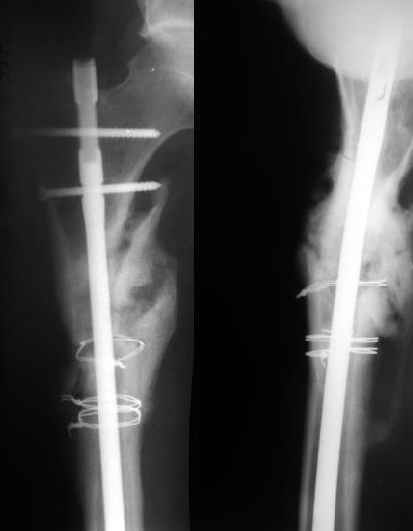

AC>Если просто закрыто перештифтовать при подобной картине, лучше с рассврливанием - это по нашему опыту дает сращение в 100%. В приложении пример - болезненное несращение более года, результат через полгода.

Еще один пример - несращение через полгода после несостоятельного остеосинтеза, и через полгода после реостеосинтеза с блокированием.

1

2